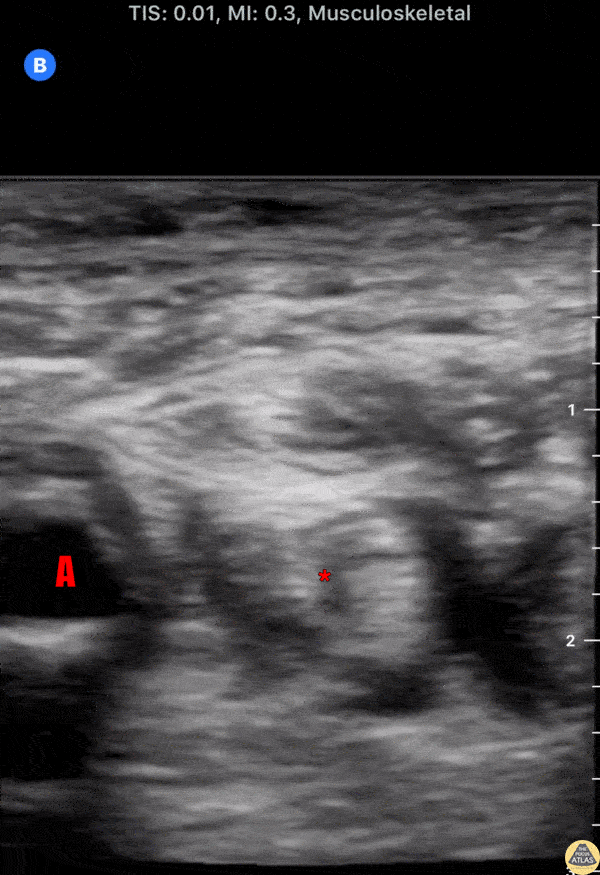

In-plane ulnar nerve block with needle entering from ulnar aspect, with anesthetic surrounding ulnar nerve. the ulnar artery (A) can be seen pulsating radially to the nerve. Dr. Peter Weimersheimer University of Vermont Medical Center